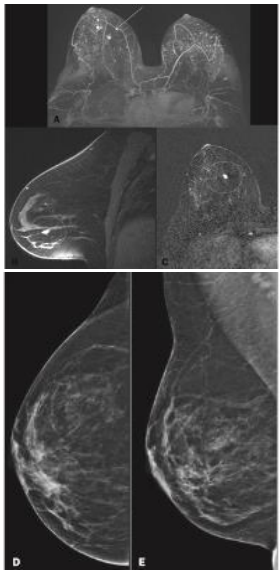

Paciente de 42 anos realizou mamografia e RM para rastreamento de câncer de mama.

Em relação ao rastreamento de câncer de mama, assinale a afirmativa correta.